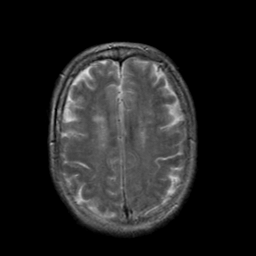

In this study, the dataset introduced in [8], which is publicly available111https://github.com/ChengBinJin/MRI-to-CT-DCNN-TensorFlow, is used for performance evaluation. It consists of 367 paired CT and MR images with the size of 512256. In the original dataset, it is noted that several CT images have stereotactic head frame that was used in Gamma Knife treatment. This head frame manually removed from the CT images. In addition, there exist various CT and MR slices that brings incredible difficulty in training the generator. Therefore, 100 images are selected from similar slices for each modality, in which 90 and 10 images are used for training and testing, respectively. Fig. 5 shows four examples of pre-processed samples.